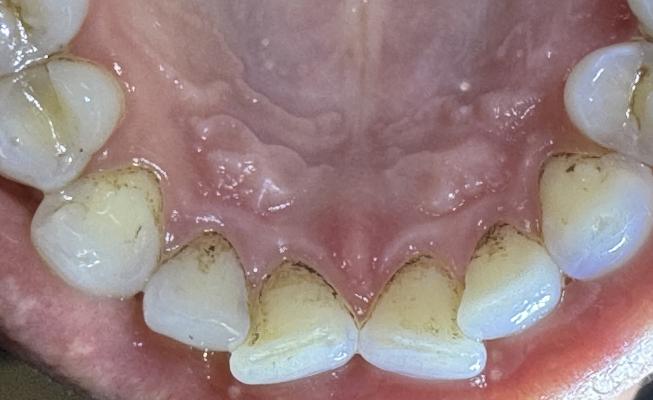

Фотографии пользователей: